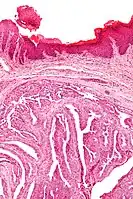

Micrograph of a papillary hidradenoma with the characteristic papillary structures and epithelium with apocrine snouts. A fragmented overlying epidermis is seen at the top of the image. H&E stain.

Micrograph of a papillary hidradenoma with the characteristic papillary structures and epithelium with apocrine snouts. A fragmented overlying epidermis is seen at the top of the image. H&E stain. a,b) Cells of lumina showed decapitation secretion similar to apocrine gland